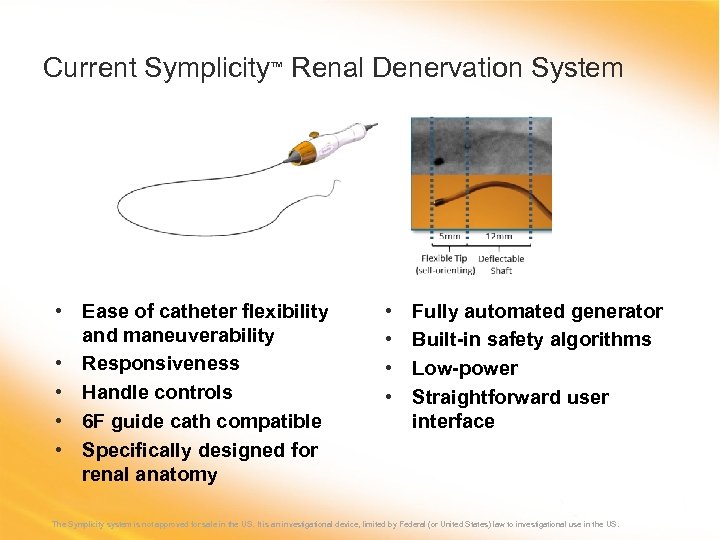

Current Symplicity™ Renal Denervation System • Ease of catheter flexibility and maneuverability • Responsiveness • Handle controls • 6 F guide cath compatible • Specifically designed for renal anatomy • • Fully automated generator Built-in safety algorithms Low-power Straightforward user interface The Symplicity system is not approved for sale in the US. It is an investigational device, limited by Federal (or United States) law to investigational use in the US.

Current Symplicity™ Renal Denervation System • Ease of catheter flexibility and maneuverability • Responsiveness • Handle controls • 6 F guide cath compatible • Specifically designed for renal anatomy • • Fully automated generator Built-in safety algorithms Low-power Straightforward user interface The Symplicity system is not approved for sale in the US. It is an investigational device, limited by Federal (or United States) law to investigational use in the US.